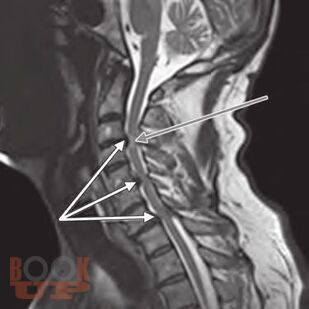

This is a unique atlas with contributions from international experts describing the most simple and advanced pain intervention techniques in a stepwise manner. The atlas provides a clear guide to identify the bony structures as seen on fluoroscopic examination enabling the operator to perform the spinal interventions safely. Remember: Bone is our Eye and Friend when performing spinal interventions under fluoroscopy. Chapters are consistently designedcovering indications, contraindications, equipment needed, and procedural stepswith the text presented in a bulleted style. Including several cases in some of the spinal intervention chapters will prepare the readers to overcome the challenges and the variability that are encountered in clinical practice. Some of the ultrasound-guided techniques described will enable readers to consider performing some pain-relief procedures in remote settings where fluoroscopy or CT guidance is not available.